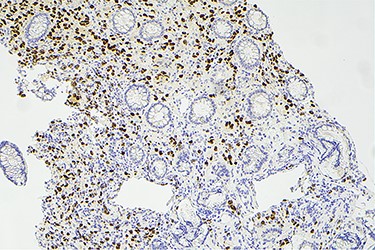

Surveillance colonoscopy in 2018 identified a fungating nonobstructing mass in the sigmoid colon (Fig. 1). Histology from a biopsy showed poorly differentiated carcinoma (Fig. 2). Given the history of breast cancer, further immunohistochemical staining was performed, which was positive for E-cadherin (Fig. 3), ER (Fig. 4), PR, GATA3 binding protein (GATA 3) (Fig. 5) and negative for Cytokeratin 20 (CK20) (Fig. 6). This confirmed metastatic invasive ductal carcinoma of breast. A positron emission tomography (PET) scan showed only the retroperitoneal mass involving the proximal sigmoid colon with no other evidence of metastatic disease (Fig. 7).

Histology slide showing positive immunohistochemical staining of estrogen receptor.

Histological examination often involves multiple markers to further assist in the diagnosis. According to the literature, helpful markers include GCDFP-15, ER, PR and GATA-3 [5, 9]. Expression of CK-7 and absence of CK-20 is also commonly seen in ductal carcinoma [10]. The immunohistochemical profile for our case was positive for E-cadherin, CK-7, ER, GATA-3 and negative for CK-20 and CDX2.